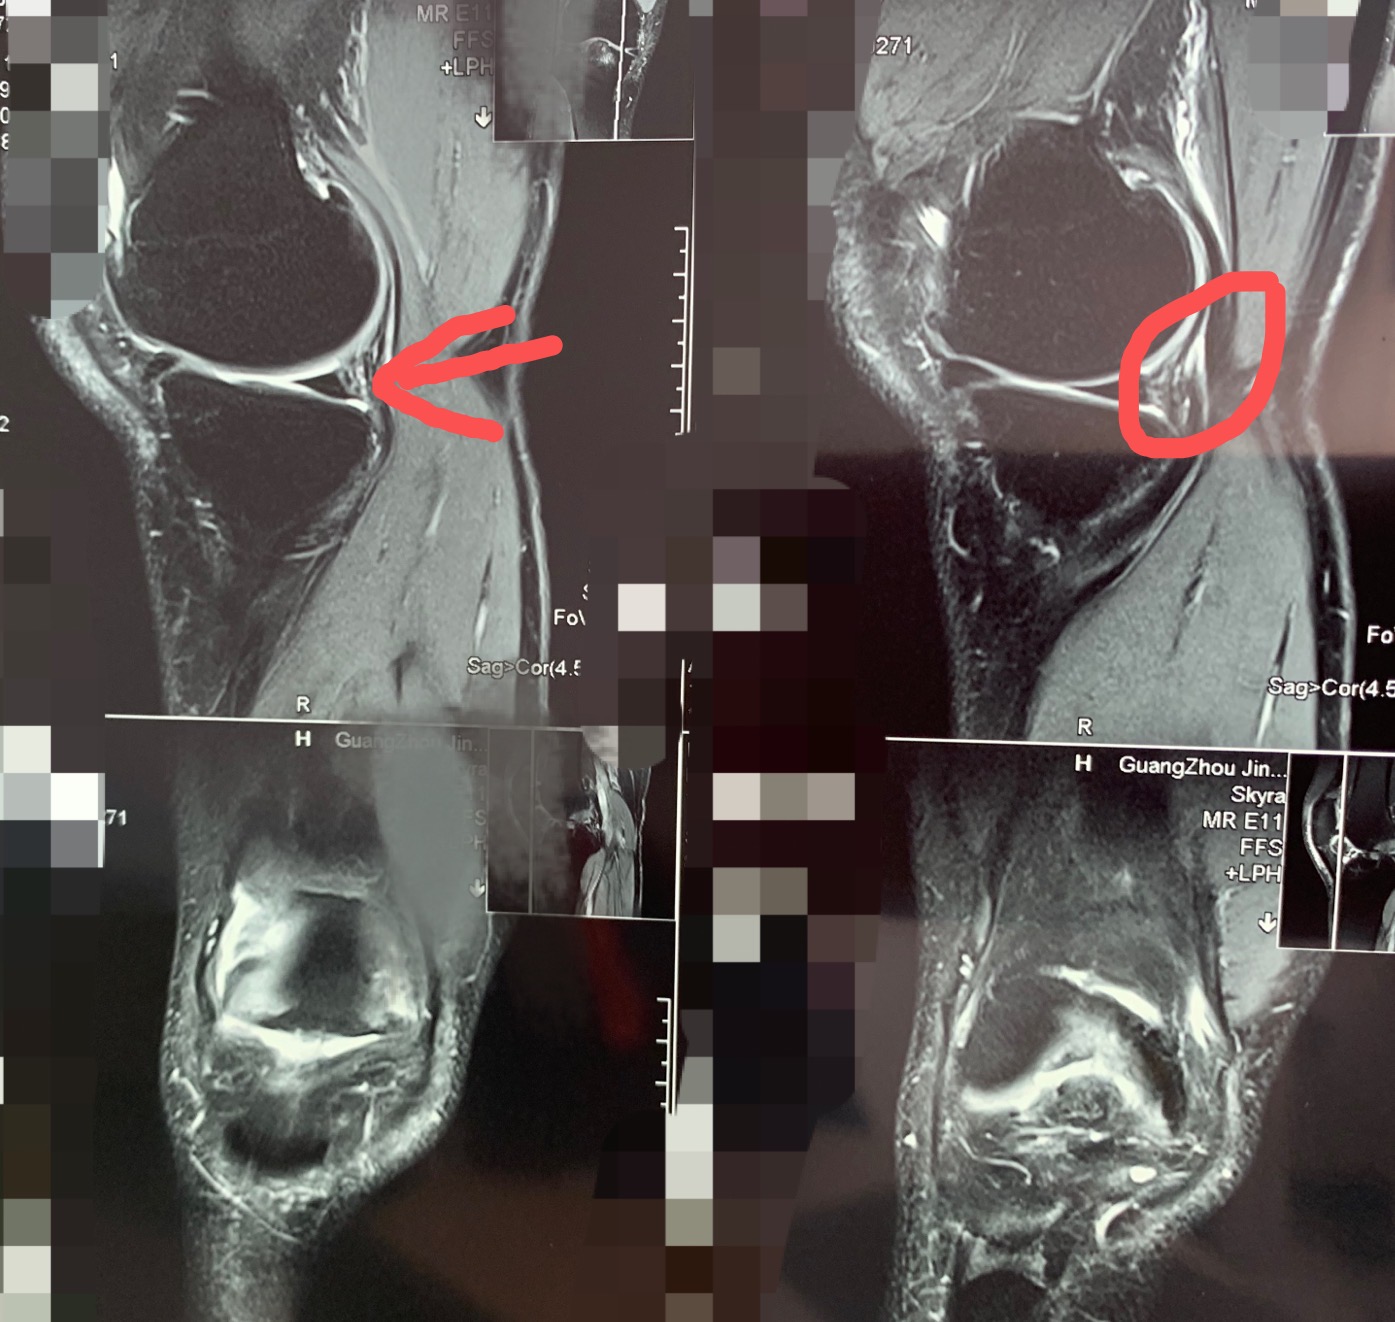

以下是他的磁共振

红色指的地方就是半月板后角损伤的地方

前十字韧带断裂明显